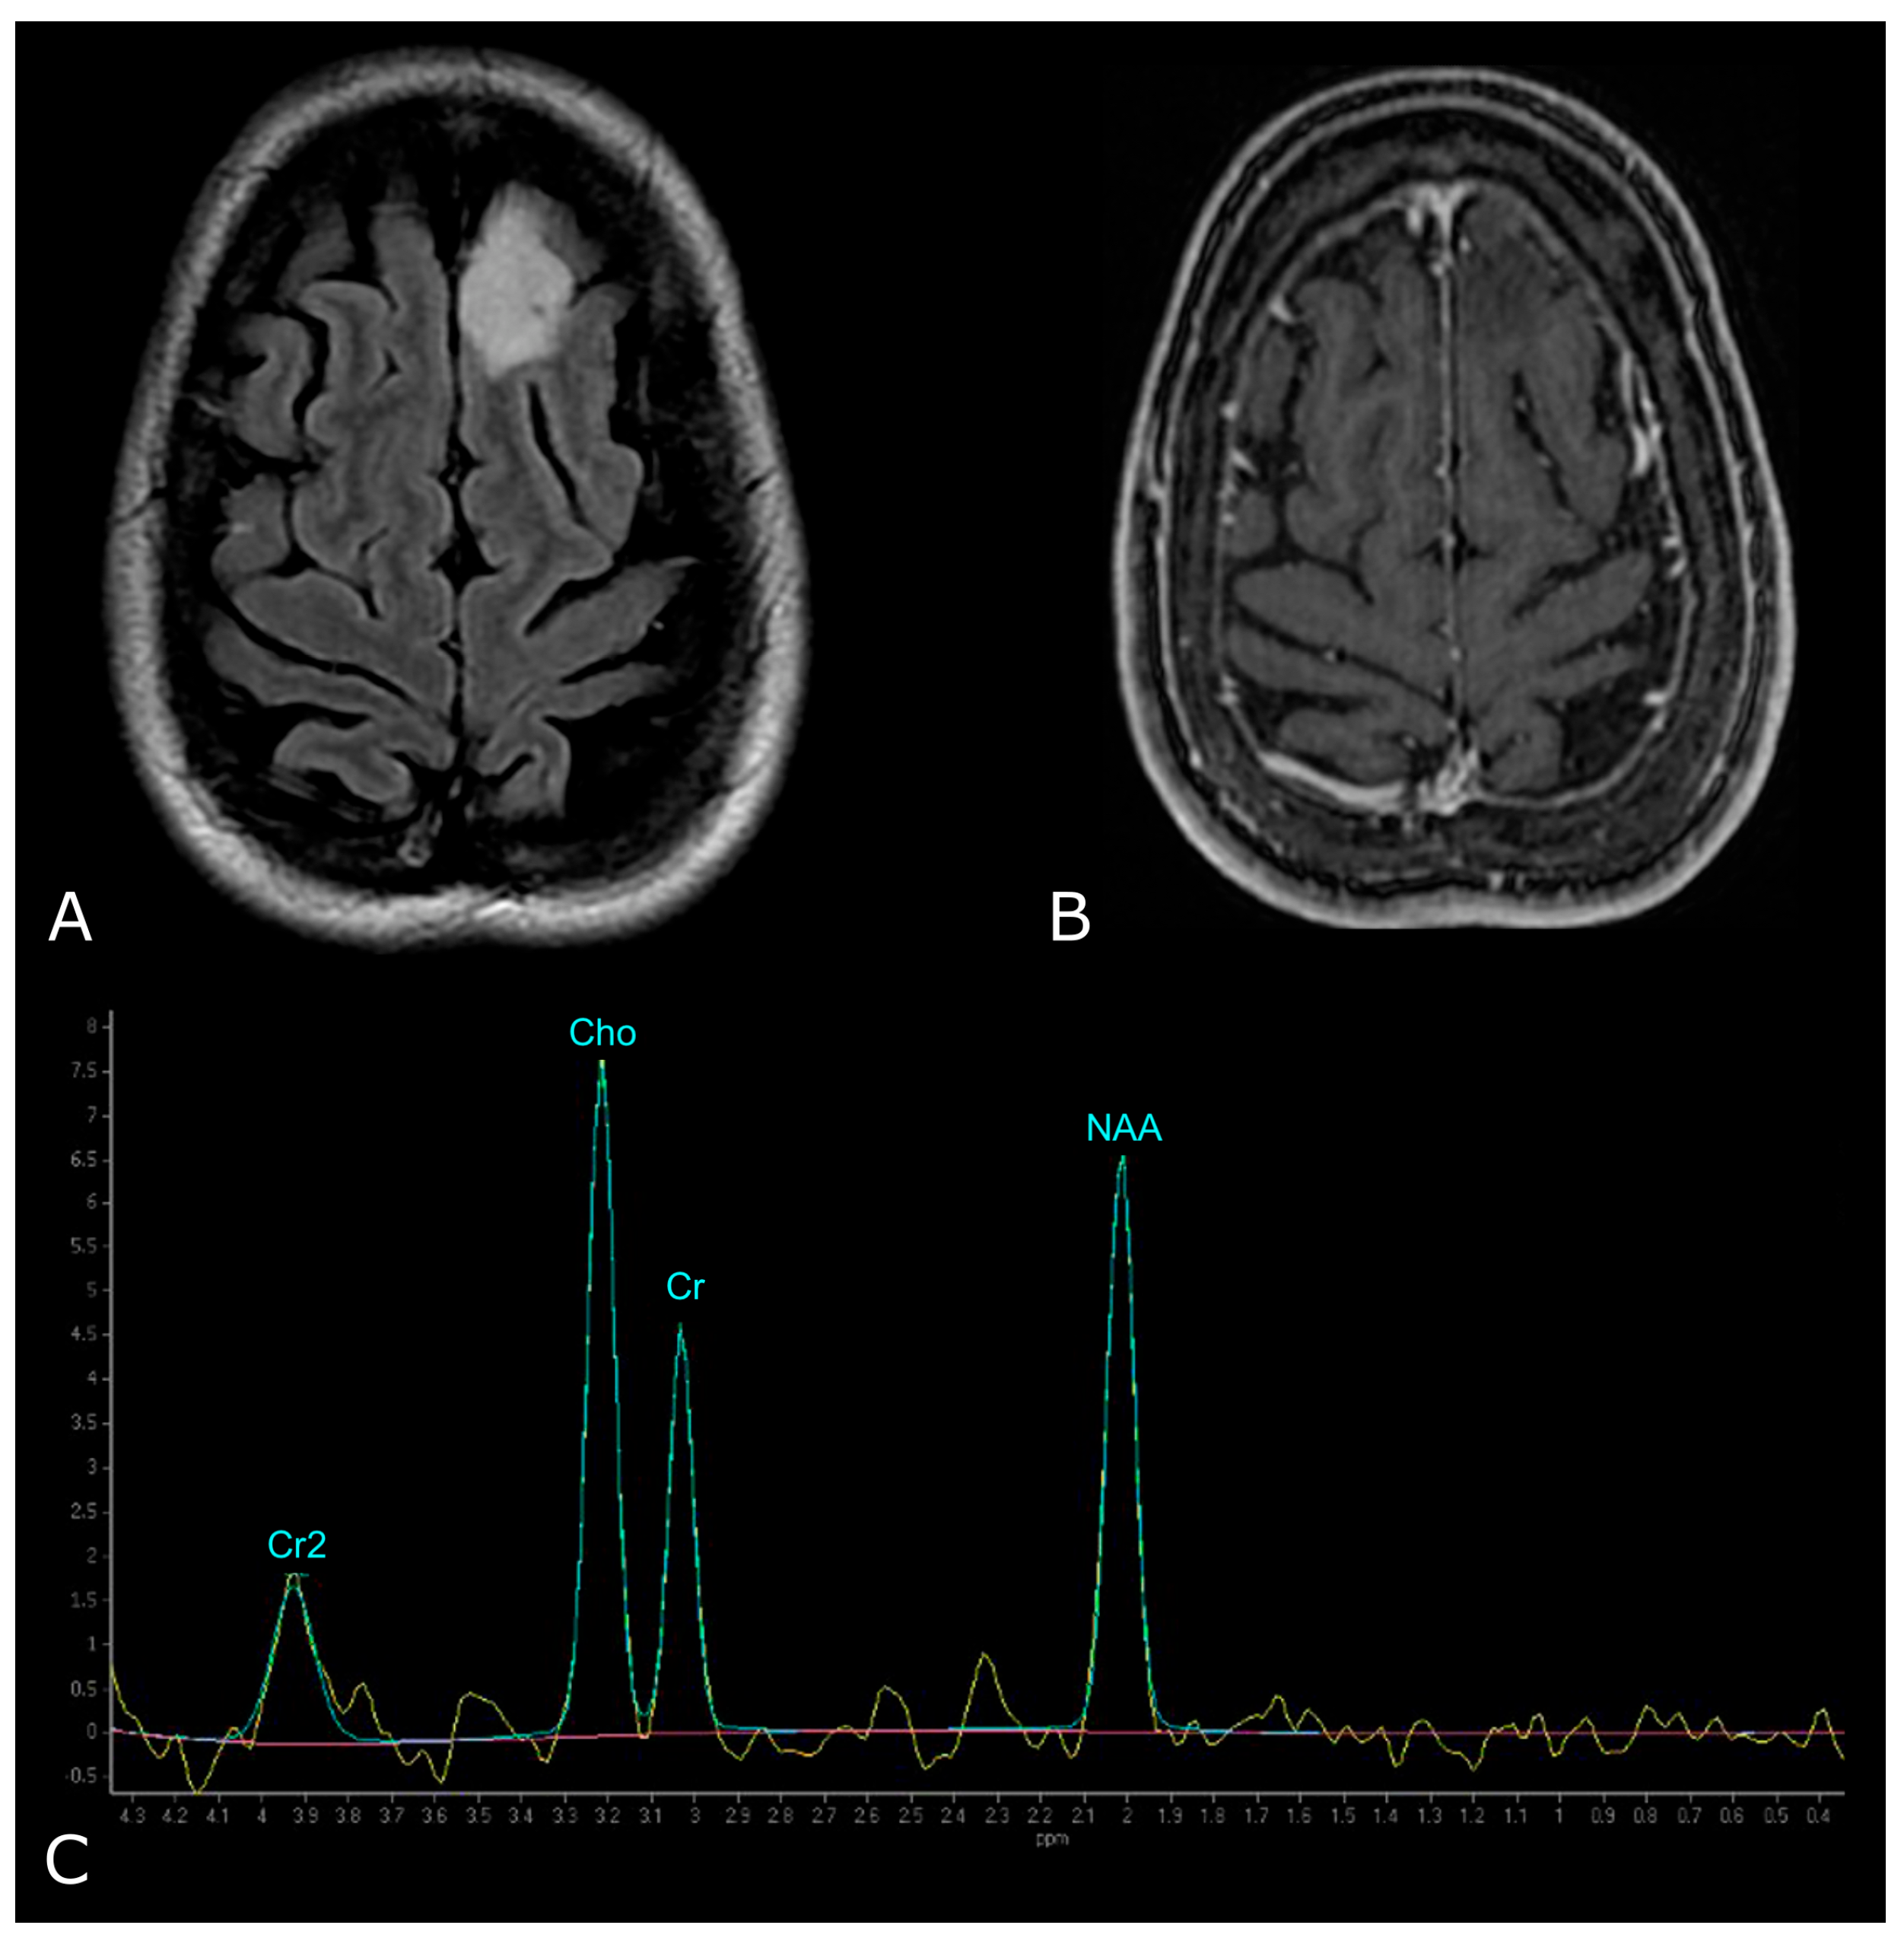

Figure 8.

Example of normal spectrum (SV TE 144ms). Normal MR spectrum demonstrating Cho, Cr and NAA peaks.

In proton MRS, the Time of Echo (TE) conditions the number of measurable neurometabolites. At short TE (e.g., TE = 35 ms or less) it is possible to detect the three main peaks normally observed in the brain—choline (Cho), creatine (Cr) and N-acetylaspartate (NAA)—and other compounds which may pathologically increase their concentration, such as myo-inositol (mI), lipids (Lip) and glutamate-glutamin (Glx). Using longer TE (TE = 144 or 280 ms), apart from Cho, Cr and NAA, it is possible to better detect the peaks of molecules with a longer T2, such as lactate (Lac) (Figure 8) [101]. The resonance peaks and biological significance of the major metabolites are listed in Table 3 [98,101,102,103]; unfortunately, there are no unequivocal cutoff metabolite signal ratios that clearly distinguish neoplastic from nonneoplastic conditions. Published MR spectroscopic results showed a sensitivity of 79% and a specificity of 77% for a choline/NAA ratio greater than 1 as an indicator of a neoplastic process [104]; the main ratios are listed in Table 4.